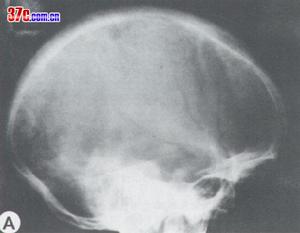

![]() | ![]() |

| 鐮狀細胞性貧血導致顱骨改變 | 鐮狀細胞性貧血導致腦改變 |